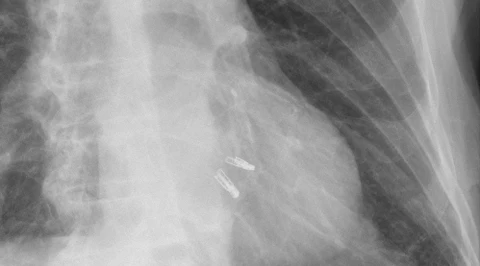

Zdjęcie RTG przedstawiające dwa urządzenia MitraClips umieszczone w sercu /Fot. Hellerhoff

GeekExtra

Pierwszy taki zabieg w Instytucie Kardiologii w Warszawie